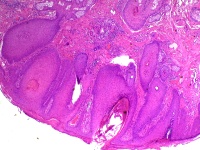

这个面部皮肤包块该怎么诊断?

性别

男

年龄

41岁

临床诊断

色素痣

一般病史

患者为41岁男性,左侧面部见一0.4*0.4cm的色素痣样肿物,行手术切除送病检。

标本名称

面部肿物

大体所见

皮肤组织,体积0.8*0.5*0.2cm,表面见直径0.2cm的灰白区,切面灰白 实性质软。

首先考虑毛鞘棘皮瘤。